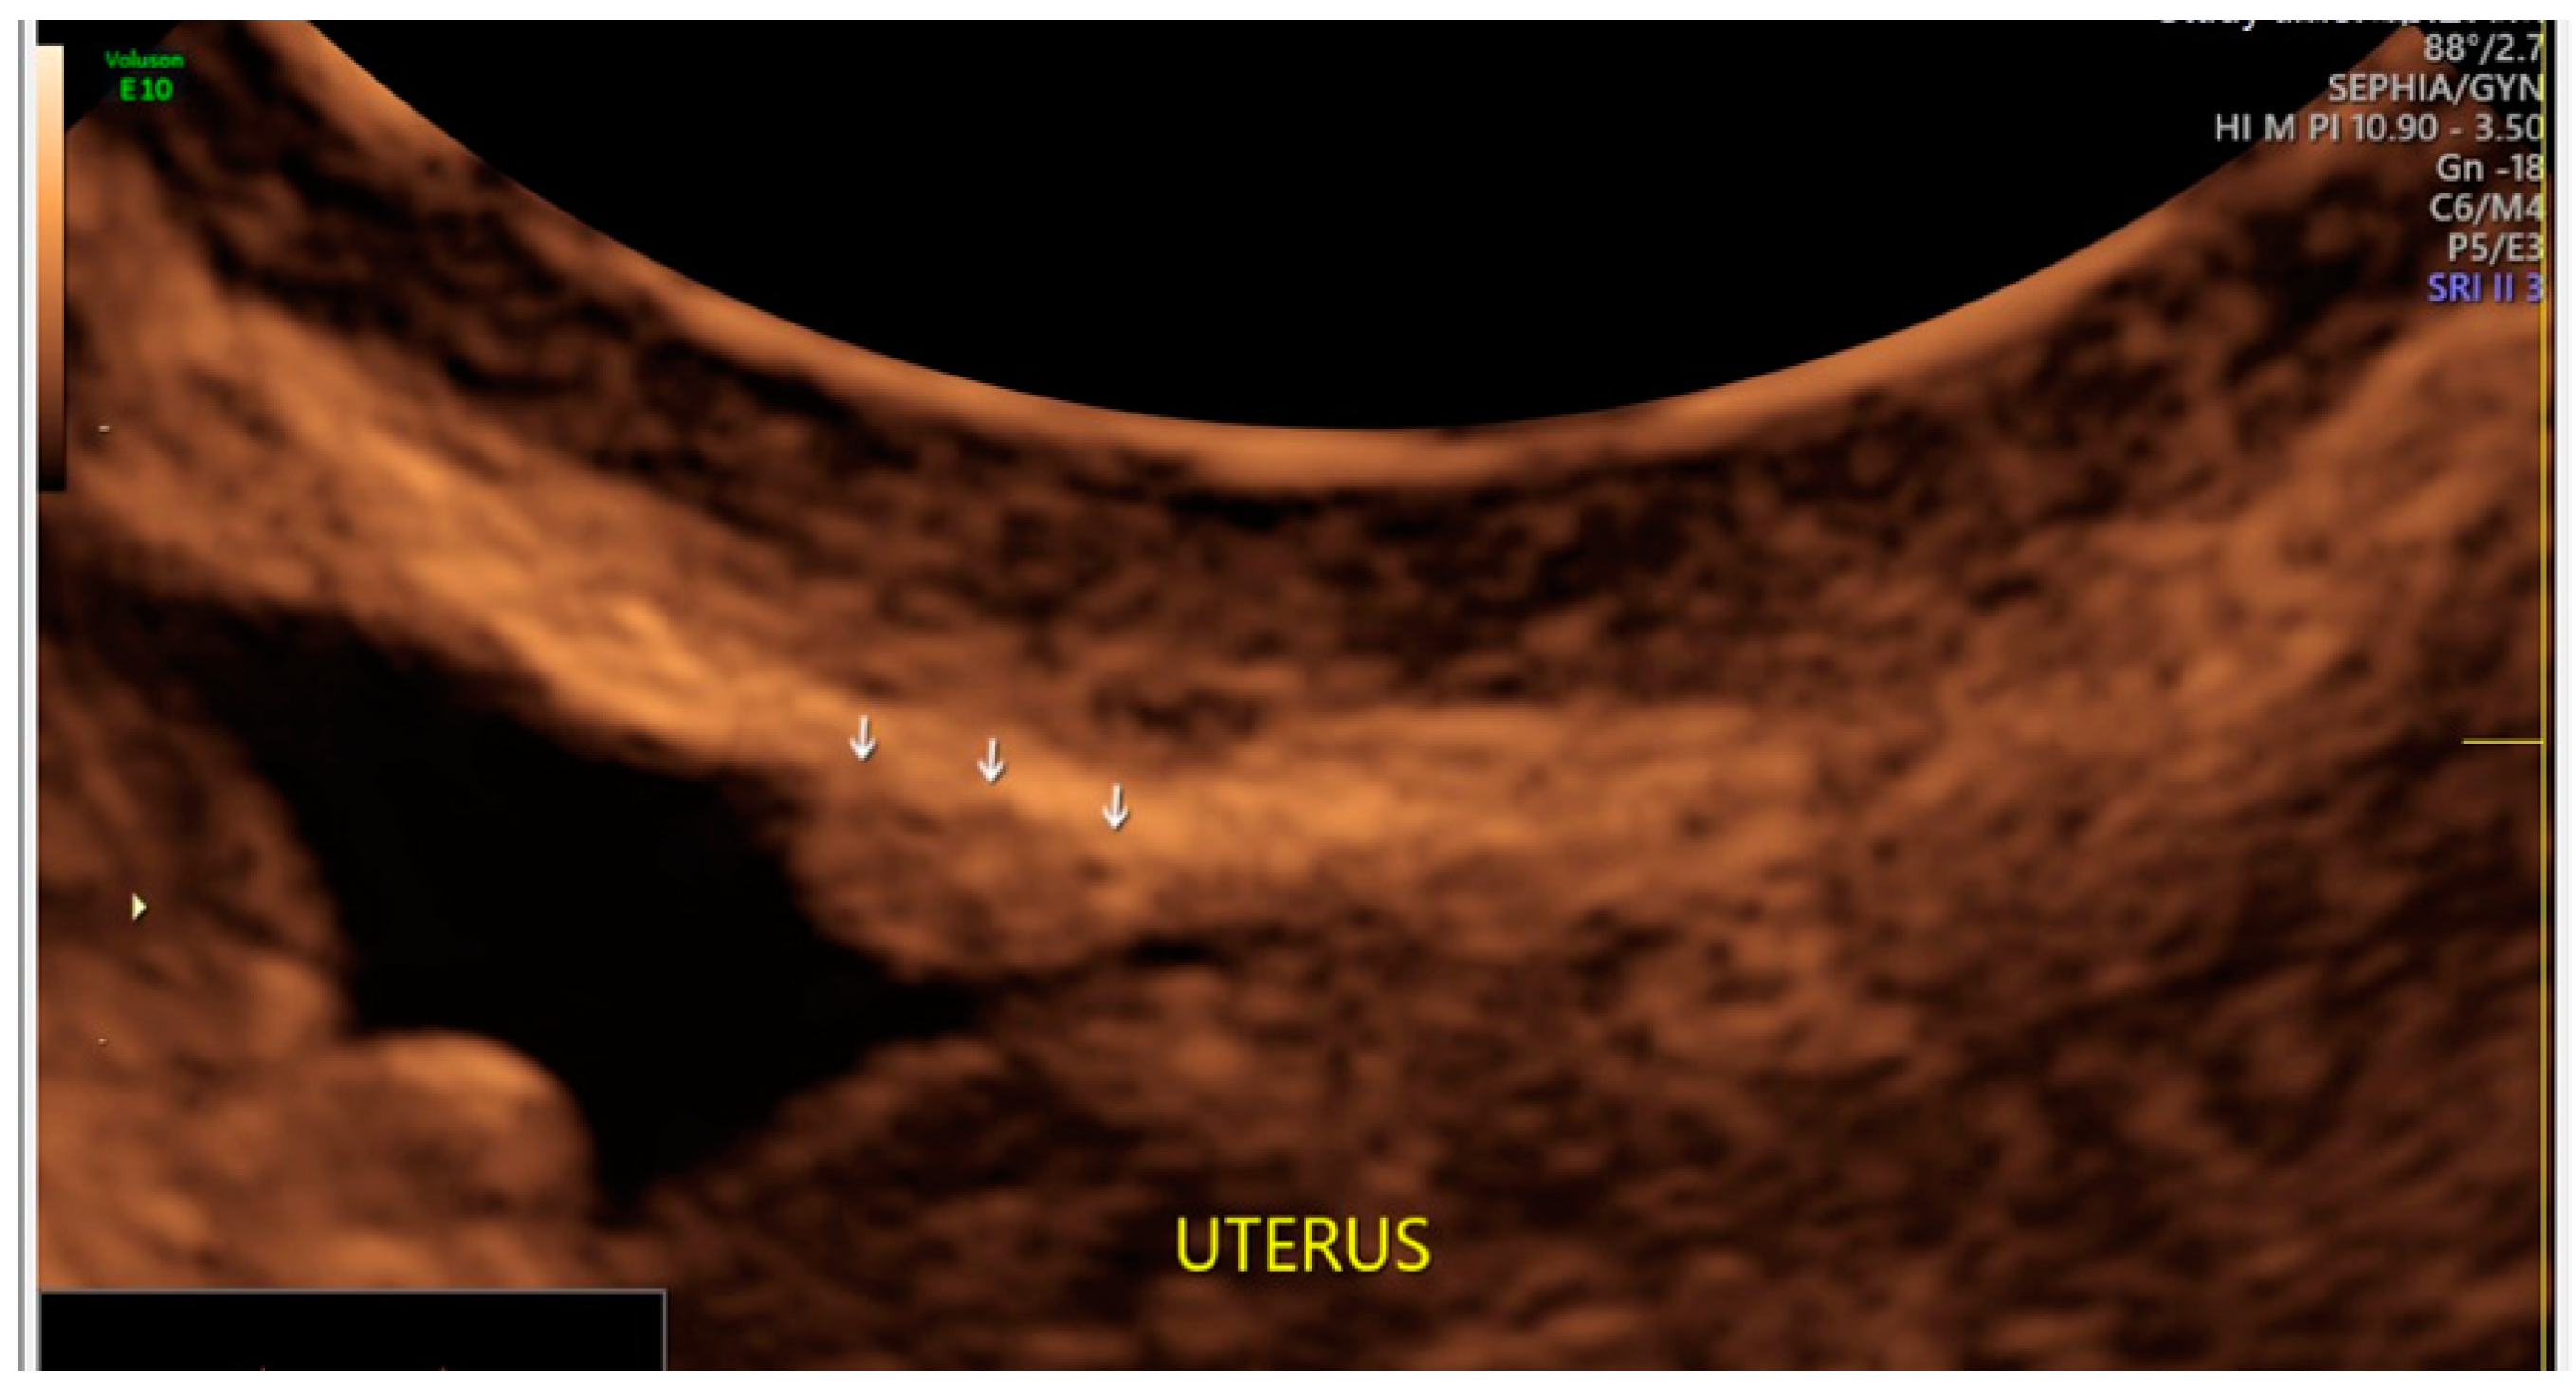

- The presence of velamentous (filmy) adhesions associated to the lesion (we called this a “veil”).